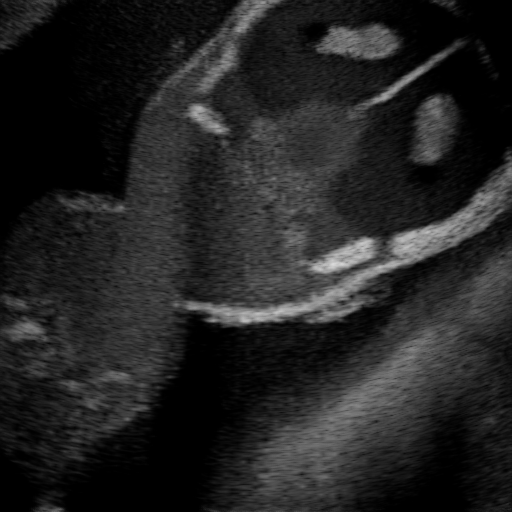

3.1 Full field-of-view Images

Above image translation has been demonstrated on patches. For the entire field-of-view (FoV) US images, patch fusion from image translation of non-overlapping patches would cause artifacts at image seams. Averaging overlapping patches, on the other hand, would blur the essential US texture. Although seamless tiling of US images is possible using graphical models [3], this requires prohibitively long computation time. Herein, we instead directly apply our trained generator on full FoV low-quality images, since the generator is fully convolutional and thus can operate on images of arbitrary size. Fig. 4 shows two examples of translated images by L2HMS and L2HMSA, demonstrating direct inference on full FoV images. While anatomical structures are well preserved and the effect of attenuation integral map is apparent, speckle texture appearance is seen to degrade slightly especially in the top image regions, where the ultrasound texture looking particularly different due to focusing difference and near-field effects.